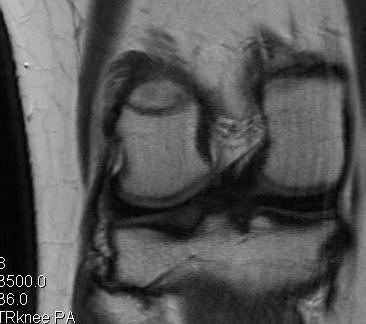

MRI

Chronic proximal avulsion LCL / Popliteus

Chronic distal avulsion LCL

Sagittal MRI showing torn ACL Coronal MRI demonstrating chronic avulsion LCL fibula head